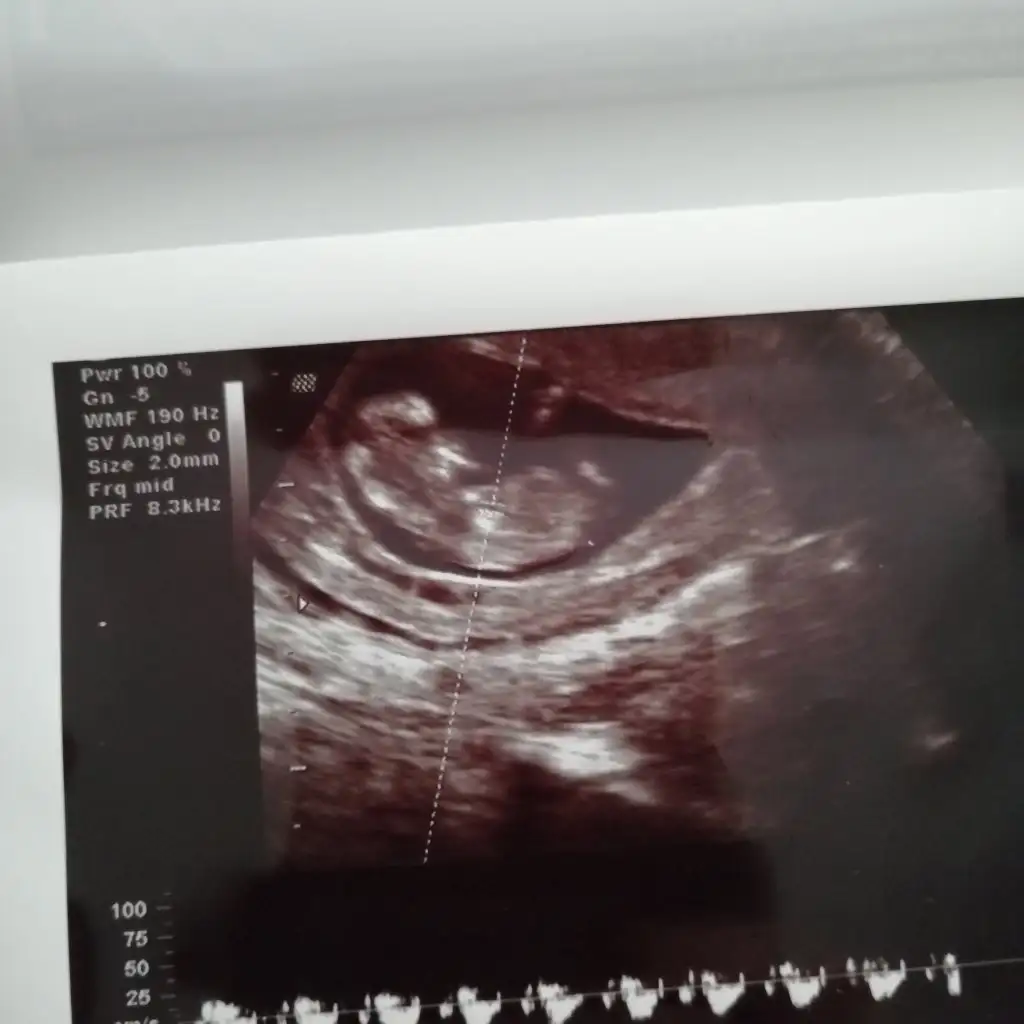

Ben bebeğimin cinsiyetini biliyorum tabi sonradan bir sürpriz çıkmazsa.. :) ama bahsettiğiniz o çıkıntı ya bakıyorum (11 ve 12. Haftalara ait birden çok usg görüntüsü var elimde) bazılarında çıkıntı kıza işaret ediyor bazılarında ise erkeğe :)Erkek ve kız için 11 yada 12 hafta usg görüntüsü olmalı açıklamalar asagıda yazıyorrabbim herkesin gönlüne göre nasip etsin inşallah .. ecmain

[/B]Eki Görüntüle 473828 gordugunuz gibi ust taraftaki simgedende anlasildigi gibi eger cikinti paralel ise kiz

yok 30°lik bir aciyla yukari dogru bakiyorsa %99 oglunuz olacak demektir simdi bi kac ornek resimler daha koyacagim kiziminkide dahil

Eki Görüntüle 473831 simdi burada cikintilara bakin eger bel popo cizgisine paralel ise kiz

yok 30 derecelik bir aciyla yukari bakiyorsa erkek